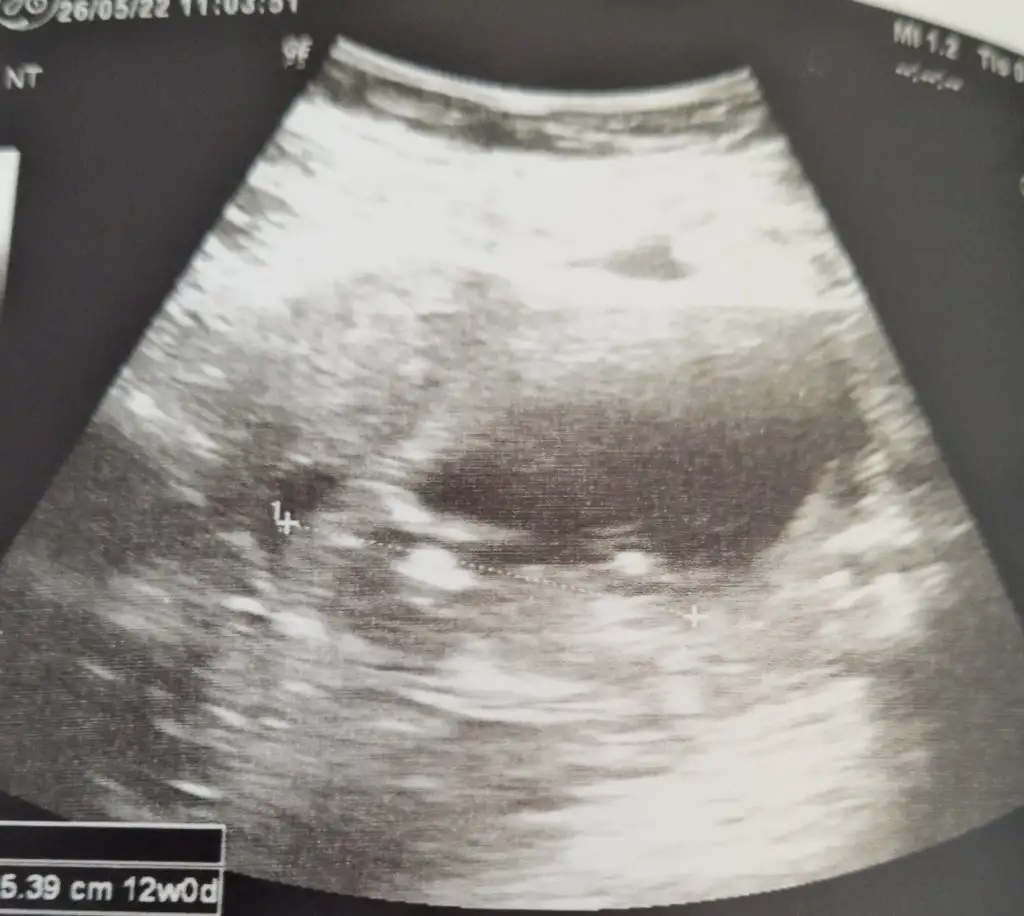

Buda ilk az once gonderdigim bugunkiydi 12 haftalik. Simdi attigim 7 haftalikValla hicbisey gormuyorum kese nerde gııı

Buda ilk az once gonderdigim bugunkiydi 12 haftalik. Simdi attigim 7 haftalik

Bunda çok anlaşılmıyor gibi ama video da var konumu böyle8 haftalık burada bebişim